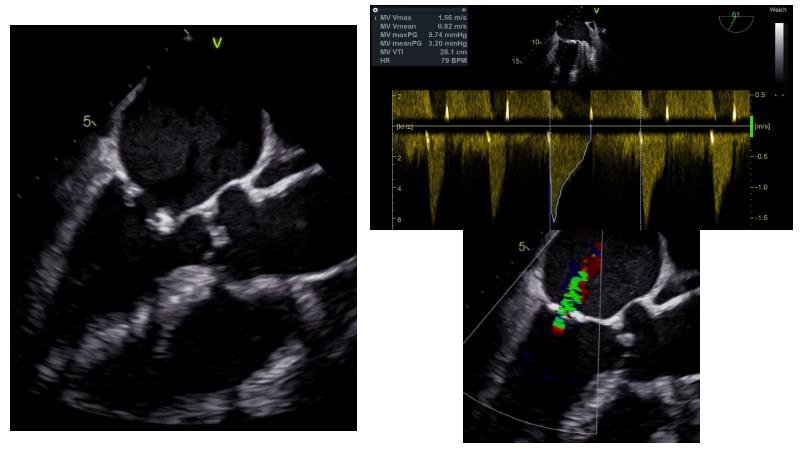

Based on an in-depth review of the data from TRILUMINATE pivotal, a randomized trial whose findings were recently published in the NEW ENGLAND JOURNAL of MEDICINE, this lecture explains how these results will impact clinical practice in the treatment of tricuspid regurgitation. Join the speakers and learn more.

- To learn how TRILUMINATE Pivotal - the first randomised trial - is impacting the clinical practice in tricuspid regurgitation treatment

- To understand how the broadest body of evidence supports TriClip therapy as first line treatment option for tricuspid regurgitation